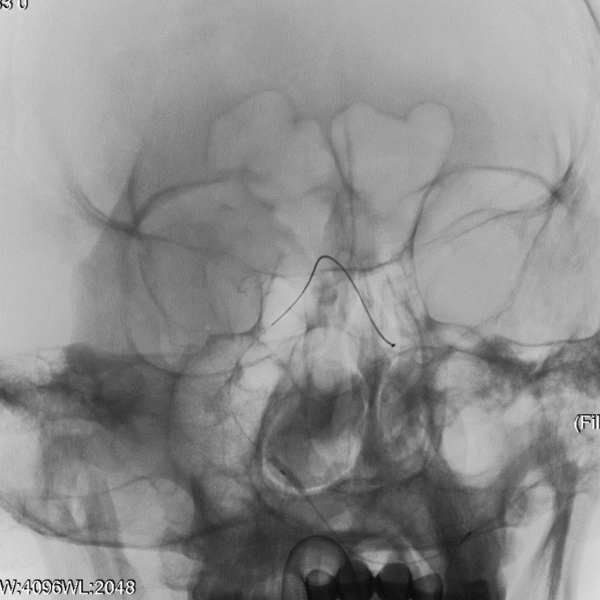

治疗过程

于左侧锁骨下动脉。

导丝怎么扩【载药时代 球扩天下】NOVA DES®颅内药物洗脱支架在症状性颅内动脉狭窄中的应用—烟台鲁东医院使用体会二例!_https://www.jmylbn.com_新闻资讯_第7张

微导丝置于大脑后动脉远端,造影显示左侧V4段重度狭窄,前向血流显著延迟。

导丝怎么扩【载药时代 球扩天下】NOVA DES®颅内药物洗脱支架在症状性颅内动脉狭窄中的应用—烟台鲁东医院使用体会二例!_https://www.jmylbn.com_新闻资讯_第8张

球囊通过病变,定位准确后扩张,压力8atm,维持30S。

导丝怎么扩【载药时代 球扩天下】NOVA DES®颅内药物洗脱支架在症状性颅内动脉狭窄中的应用—烟台鲁东医院使用体会二例!_https://www.jmylbn.com_新闻资讯_第9张

置入赛诺神畅 NOVA DES®内药物洗脱支架2.5*12mm,压力12atm,维持30S。